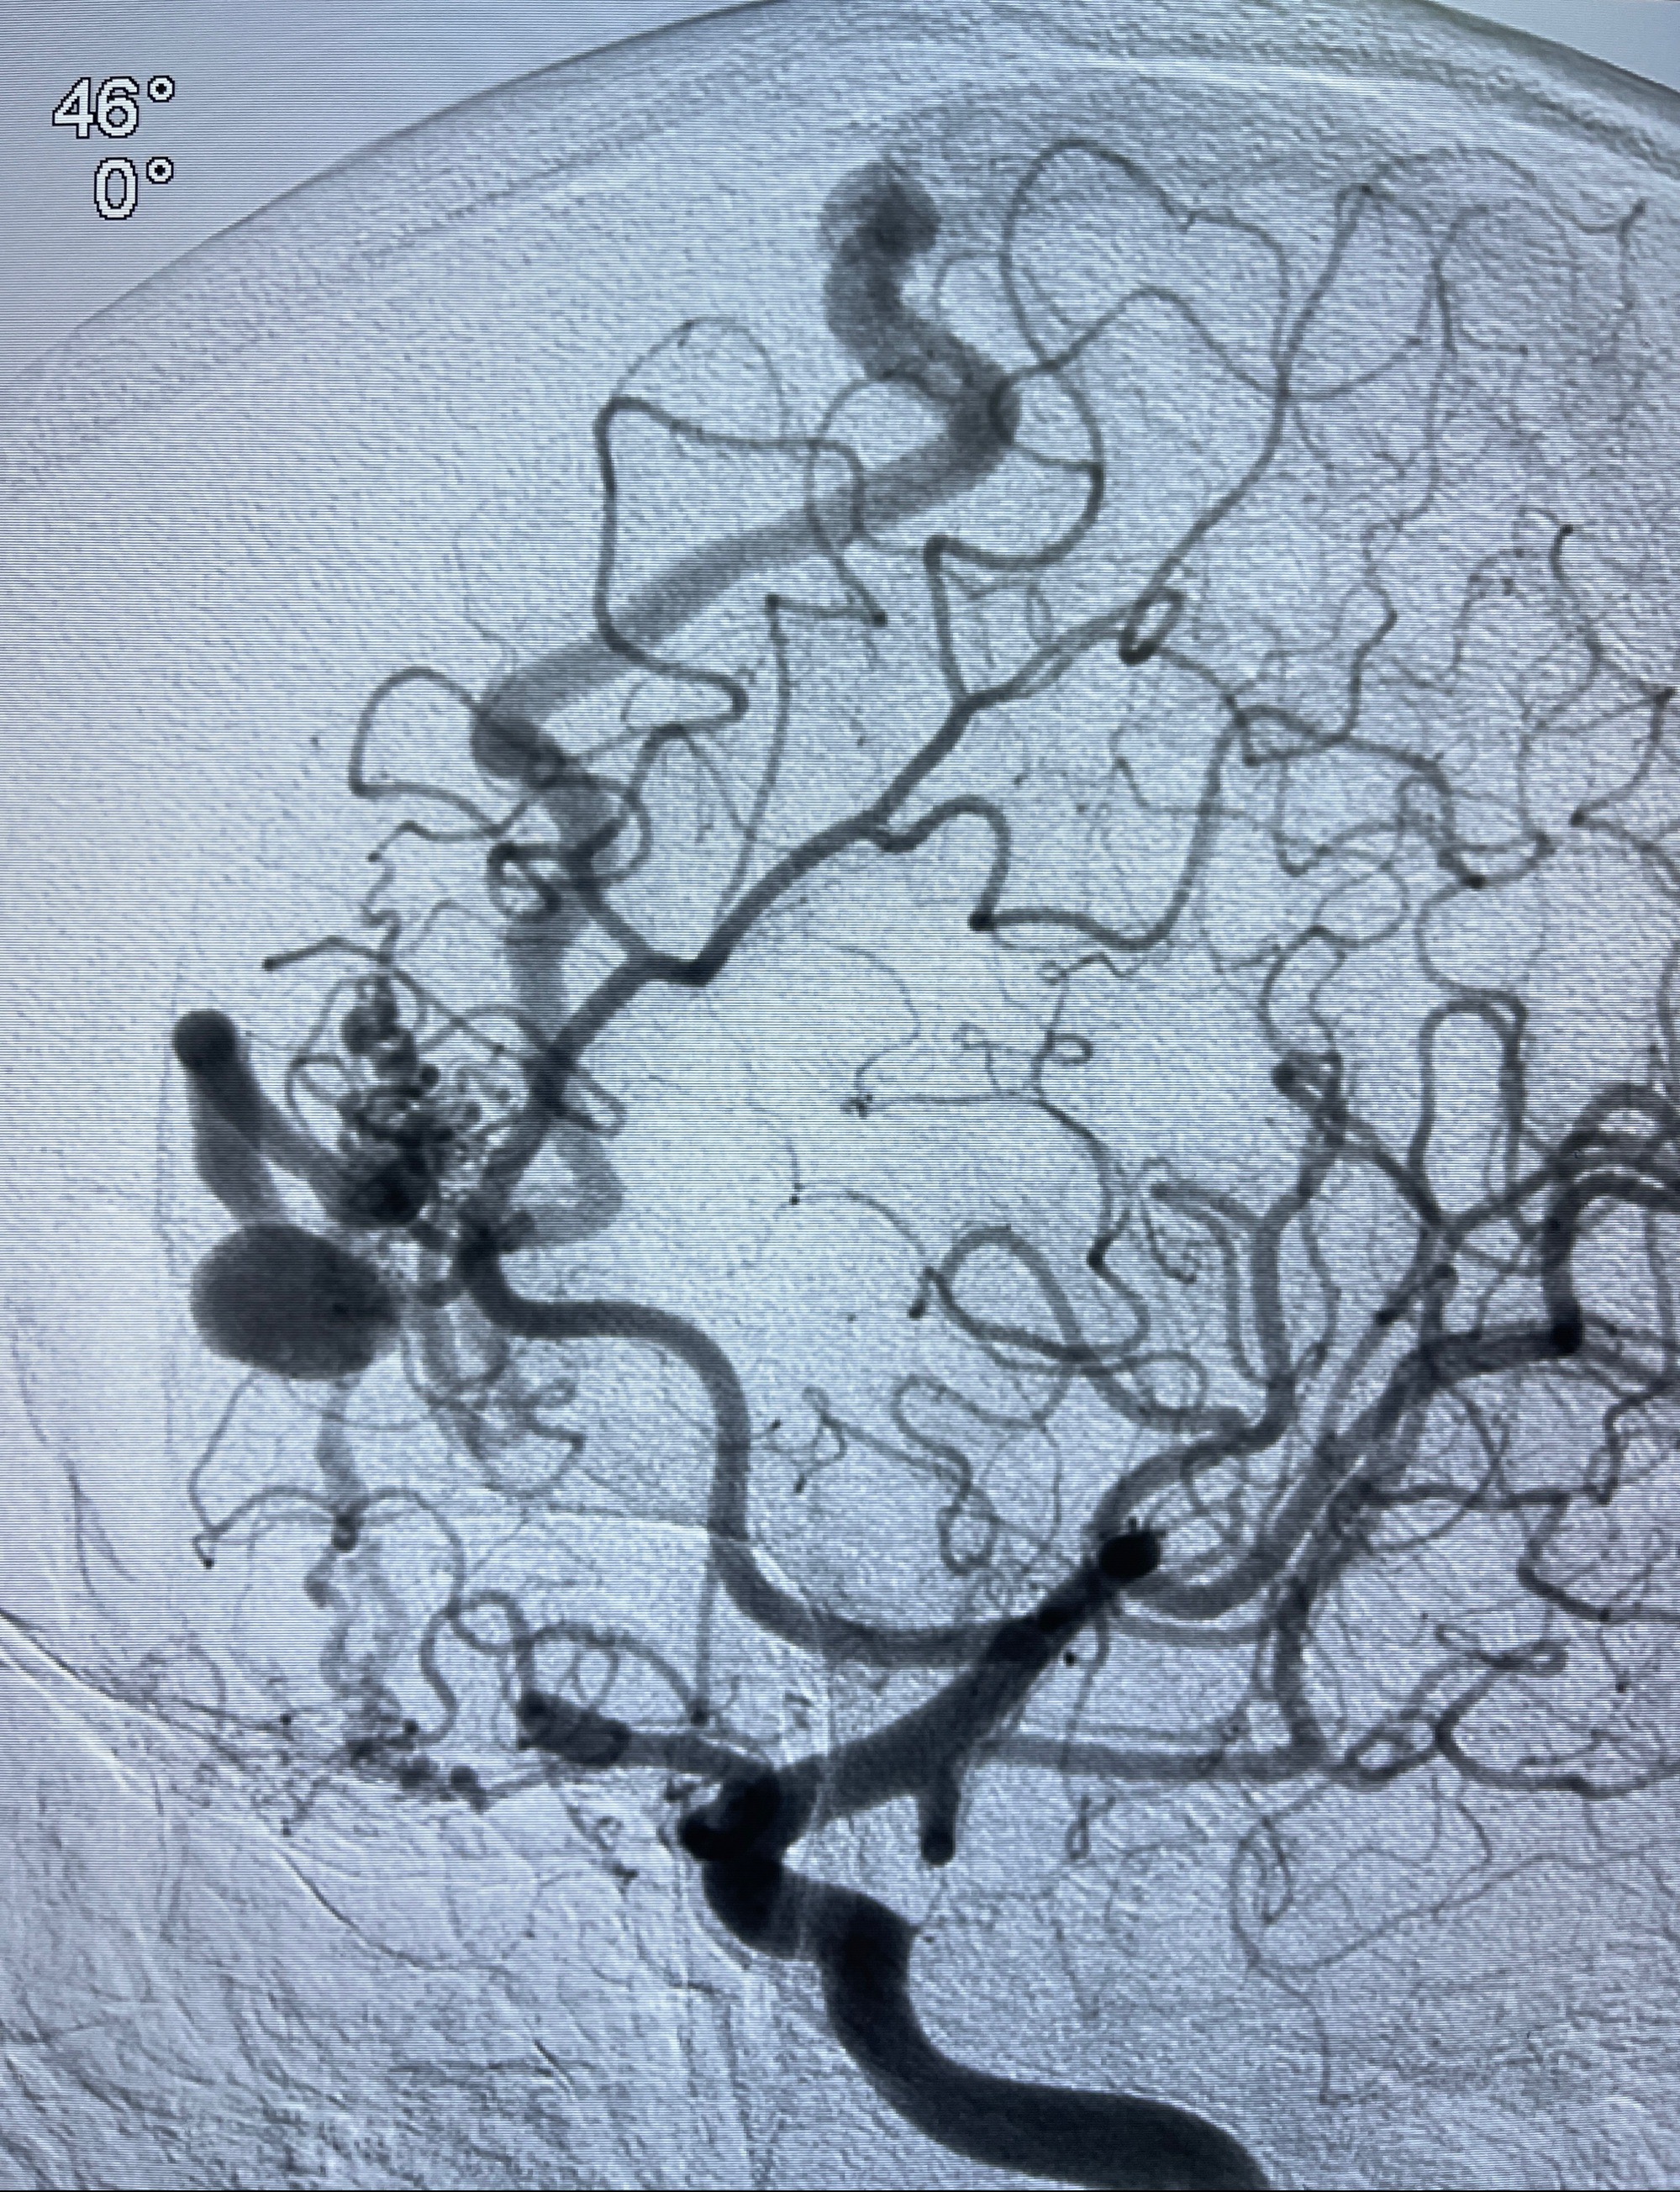

2023年8月21日]景德镇市第一人民医院脑血管造影检查,提示:主动脉弓、双侧颈总动脉、锁骨下动脉造影未见异常,左侧大脑前动脉静脉瘘。

2023-09-13全脑血管造影:前颅底硬脑膜动静脉瘘,供血动脉为双侧胼周动脉、眼动脉脑膜支,静脉向上矢状窦方向引流